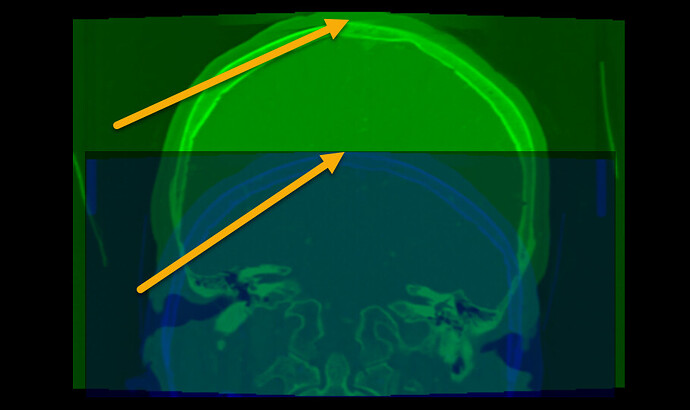

• Most registration methods generally require the images cover the same region. Your images do not meet this requirement. To fix this, probably the easiest is to crop the images to approximately to the same region.

• The image edges coincide edge of anatomy (skull touches the image edge). This is an issue because image processing methods often need to extrapolate a little bit beyond the image region and this extrapolation will fail if the intensity near the image edge is non-uniform (it is fine if the image edge cuts through the middle of tissue or cuts through the middle of air, but the image edge should not be at an anatomical region boundary).

result: